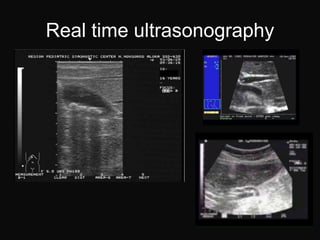

Real time ultrasonography